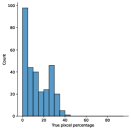

The main purpose of these experiments is to find the effect of using synthetic data generated from the SinGAN-Seg pipeline instead of small real datasets because the SinGAN-Seg pipeline can generate an unlimited number of synthetic samples per real image. A synthetic sample consists of a synthetic image and the corresponding ground truth mask. Therefore, experts’ knowledge is not required to annotate the ground truth mask. For these experiments, we have selected the best parameters of the SinGAN-Seg pipeline from the experiments performed under Section Synthetic data versus real data for segmentation. First, we created small sub-datasets from the real polyp images from fold one such that each dataset contains number of images, where can be one of the values of . The corresponding synthetic dataset was created by generating synthetic images and corresponding masks per real image. Then, our synthetic datasets consist of number of images such that . Then, we have compared true pixel percentages of real masks and synthetic masks generated from the SinGAN-Seg pipeline using histograms of bin size of . The histograms are depicted in Fig 10. The first row represents the histograms of real small detests, and the second row represents the histograms of corresponding synthetic datasets. Compare pairs (one from the top row and the corresponding one from the bottom) to get a clear idea of how the generated synthetic data improved the distribution of masks.

The UNet++ segmentation models were trained using these real and synthetic datasets separately. The synthetic dataset is generated using style transfer ratio because it shows the best performance in the experiment, which uses only fake data to train segmentation models as presented in Table 2 in addition to the best SIFID values presented in Table 1. Then, we have compared the performance differences using validation folds. In these experiments, the training datasets were prepared using fold one. The remaining two folds were used as validation datasets. The collected results from the UNet++ models trained with the real datasets and the synthetic datasets are tabulated in Table 3. A comparison of the corresponding IOU scores are plotted in Fig 11.